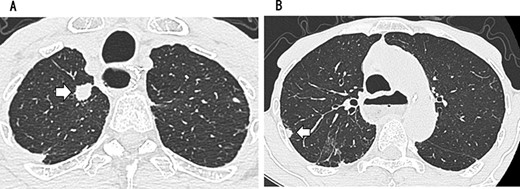

A 79-year-old man underwent right subthoracic esophagectomy and posterior mediastinal reconstruction for esophageal cancer (squamous cell carcinoma, pT3N4M0 Stage IVa) 9 years ago. The patient had previously undergone four cycles of CDDP+5-FU. After esophagectomy, the patient developed ileus three times; it was conservatively managed. During the third hospitalization, chest computed tomography (CT) showed a circular nodule measuring 1.4 cm in the S1 apex of the right upper lobe and a nodule measuring 0.9 cm outside S2 (Fig. 1). No findings were suggestive of esophageal cancer recurrence. 18F-Fluorodeoxyglucose-positron emission tomography revealed FDG uptake increated in the nodule in the right lung S1 with a maximum standardized uptake value of 4.3 and in the nodule in the right lung S2 with a maximum standardized uptake value of 2.7. No significant hilar or mediastinal lymph node swelling or distant metastases were detected. Bronchoscopic biopsy did not reveal any signs of malignancy. Based on the above findings, we suspected multiple lung metastases secondary to esophageal cancer, metachronous primary lung cancer or intrapulmonary metastasis secondary to primary lung cancer. We performed partial resection of the two nodule in the upper lobe of the right lung for diagnosis and treatment. Histopathological examination revealed squamous cell carcinoma (Fig. 2). Immunostaining was performed to determine whether the primary organ was the esophagus or the lung, but no diagnosis was made. On request, no additional chemotherapy was administered. Chest CT after 1 year and 2 months of right lung resection revealed a nodule measuring 1.5 cm at the apex of the left lung and a nodule measuring 0.9 cm below the S9 pleura of the left lung (Fig. 3).

CT showing a circular nodule measuring 1.4 cm in the S1 apex of the right upper lobe (A) and a nodule measuring 0.9 cm outside S2 (B).